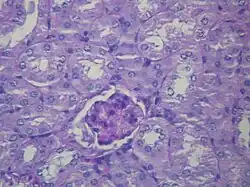

_HE.jpg)